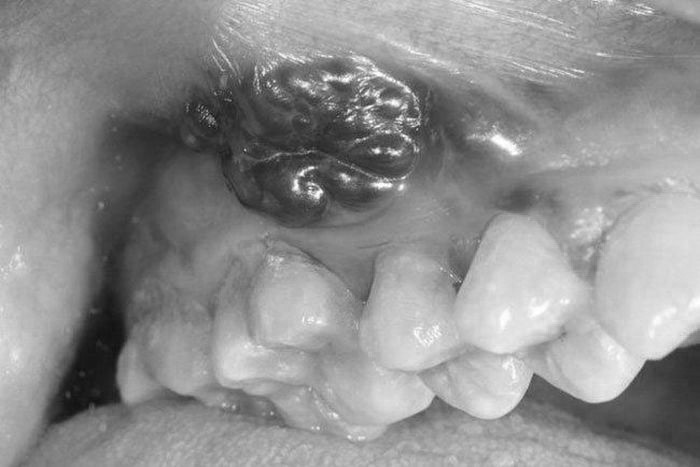

Bệnh nhân là ông Nguyễn Văn N. (71 tuổi, trú ở Nam Định) vào viện trong tình trạng u to lấp đầy miệng khiến người bệnh không ăn uống được. Sáu tháng trước, ông N. thấy trong miệng xuất hiện khối sùi loét, đau, ăn uống vướng. Nhưng bệnh nhân nghĩ bị nhiệt miệng nên không khám.

Hai tuần trước khi nhập viện, khối u phát triển nhanh khiến ông N. không ăn, không nói được, thỉnh thoảng chảy máu qua đường miệng. Người nhà đã đưa đi khám tại tuyến dưới. Bác sĩ nghi ngờ ông N. bị ung thư nên chuyển tuyến lên Bệnh viện K.

Các xét nghiệm lâm sàng và cận lâm sàng cho thấy ông N. mắc ung thư lợi hàm dưới, có tiền sử hút thuốc lá và uống rượu nhiều năm. Bệnh nhân được chỉ định phẫu thuật để xử lý vét hạch cổ, cắt rộng u, cắt đoạn xương hàm dưới, tạo hình.